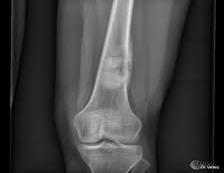

Los tumores óseos suelen aparecer en zonas de hueso que crecen rápidamente (Metáfisis). Podemos clasificarlos en diferentes subtipos:

El diagnóstico de los sarcomas óseos se basa en los siguientes exámenes: Historial médico y exámenes clínicos

Examen radiológico.

Se usa una amplia gama de técnicas de adquisición de imágenes para poder ver dentro del cuerpo y determinar el alcance de un sarcoma óseo y establecer la presencia o ausencia de enfermedad metastásica distante.

1. Rayos X

Examen histopatológico

El examen histopatológico, es decir, el examen de tejidos en un microscopio, se lleva a cabo sobre una biopsia o porción de tejido tras la extirpación de todo el tumor por cirugía. Sólo la evaluación histopatológica del tumor revelará si el tumor es un sarcoma óseo y, en su caso, de qué tipo. También proporcionará el “grado de malignidad”, esto es, una clasificación de la agresividad de las células del cáncer.